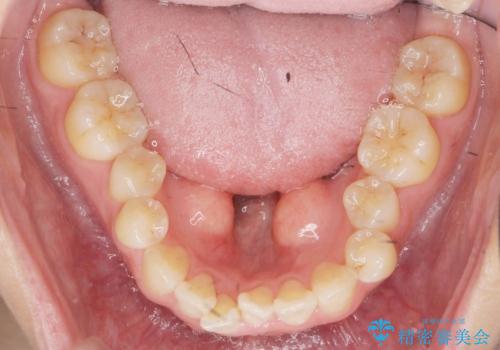

上下の歯のがたつきを改善するマウスピース矯正治療と、下顎に見られる大きな骨隆起を外科的に除去する治療計画を進めていきます。

骨隆起の除去は、静脈内鎮静法を用いてほとんど記憶のないうちに行うことができます。

歯並びが改善したとともに、骨隆起を除去したことで舌をしまうスペースも増え安定した口腔内環境を確立することができました。